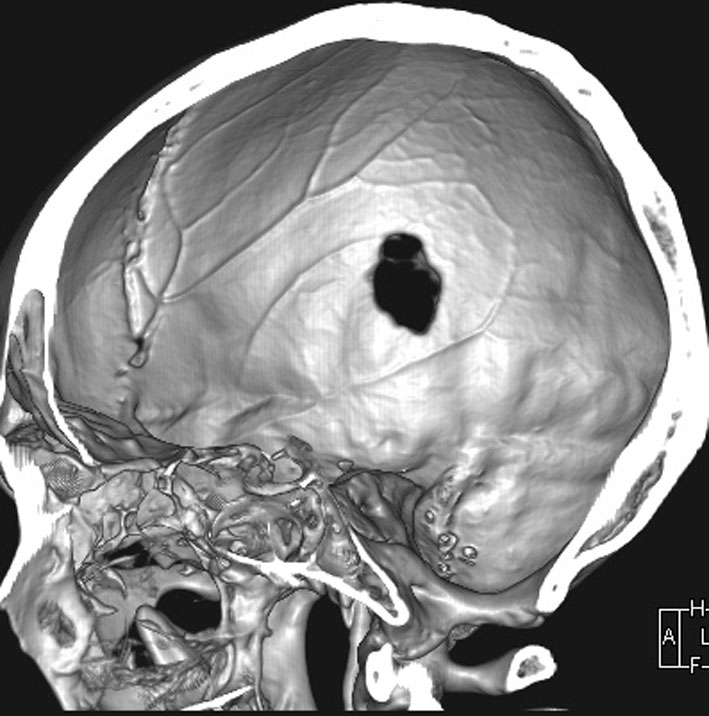

CTで典型的な頭蓋骨の打ち抜き像 punched out lesion が左頭頂骨にあります。これだけでLCHと診断がつくような画像です。

頭蓋骨のLCH

- 上の写真は,子供の右の頭頂骨にできたLCHで,頭部病変では最も多く見られるタイプです

- 頭蓋骨が丸く抜けるように破壊されるのでpunched out lesionと表現されます

- 頭蓋骨欠損がそれほど大きくないものは様子を見ます

- 自然に消失して治ってしまうことも多いです

- 単臓器単発型は無治療で経過をみるというのもよいでしょう

生検術だけして経過を見ると骨欠損が修復される

中年の女性の頭頂部に発生したものです。症状は頭皮の膨隆でした。生検術でLCHと診断して,しばらく経過を見たら自然退縮しました。

左は発症時,右は2年後のCTです。骨欠損部は自然修復されています。LCHの小さな骨欠損は頭蓋形成しなくても良いです。